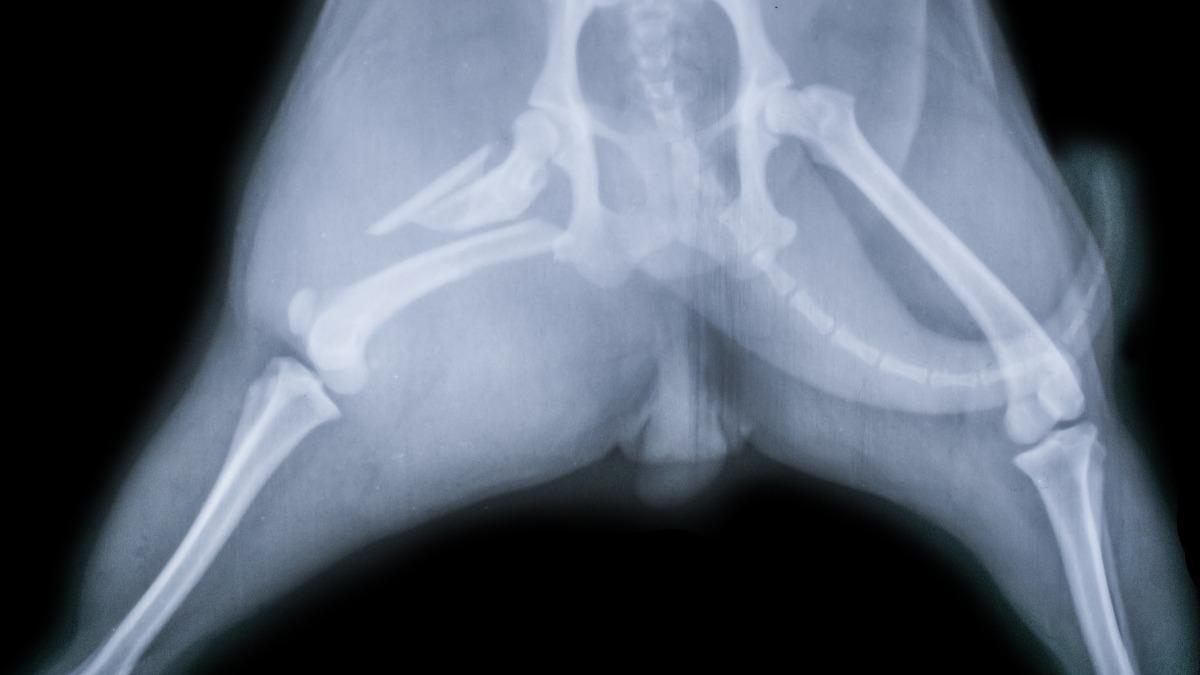

An X-ray is a non-invasive imaging technique that utilizes radiation to create images of your pet's internal structures, such as bones and joints. This method allows veterinarians to identify fractures, tumors, and other abnormalities that may be affecting your pet's health.

There are various reasons your veterinarian may suggest an X-ray for your pet. Common situations include assessing injuries from accidents, diagnosing conditions like arthritis or hip dysplasia, and investigating unexplained symptoms such as vomiting or difficulty breathing. An X-ray can provide important information that helps us develop a comprehensive treatment plan for your pet.